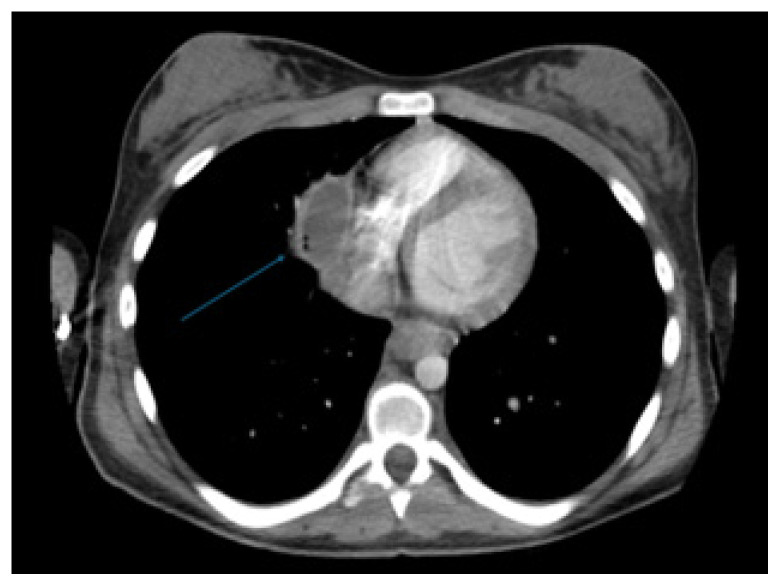

A Case Report of a Mediastinal Granuloma Related to Histoplasmosis with Streptococcus dysgalactiae Subspecies equisimilis Superinfection Resulting in Abscess and Subsequent Pericarditis in a Pediatric Patient.

Abstract Image